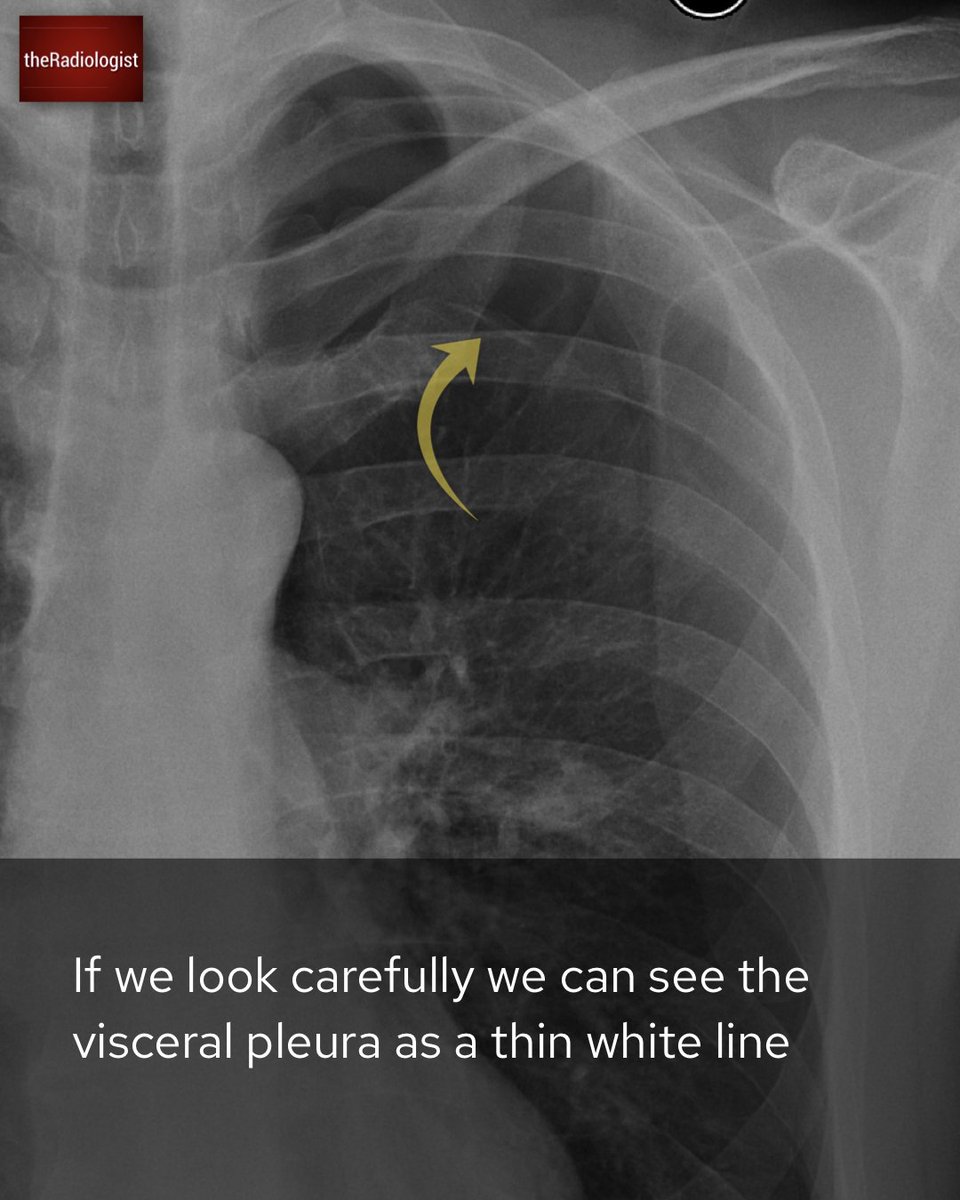

What is the most pressing abnormality on this X-Ray? Open thread for the explanation.

Explanation 3/3

Explanation 2/3

Explanation 1/3